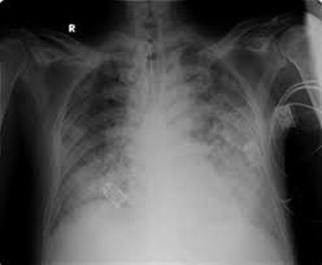

Se produce cuando el infarto afecta a más del 25 % del ventrículo izquierdo y la presión capilar pulmonar es > 25 mmHg.

Se indica furosemida en bolo EV ( precarga).

Tenemos el score de Killip que establece una clasificación clínica radiológica al ingreso del paciente con SCACEST.

Clase Hallazgos clínicos Mortalidad I Sin signos ni síntomas de 0 a 5%

estertores o crepitantes, 3er ruido o aumento de PV

10 a 20%

Edema pulmonar 35 a 45%

Shock cardiogénico: hipotensión y vasoconstricción periférica

85 a 95%